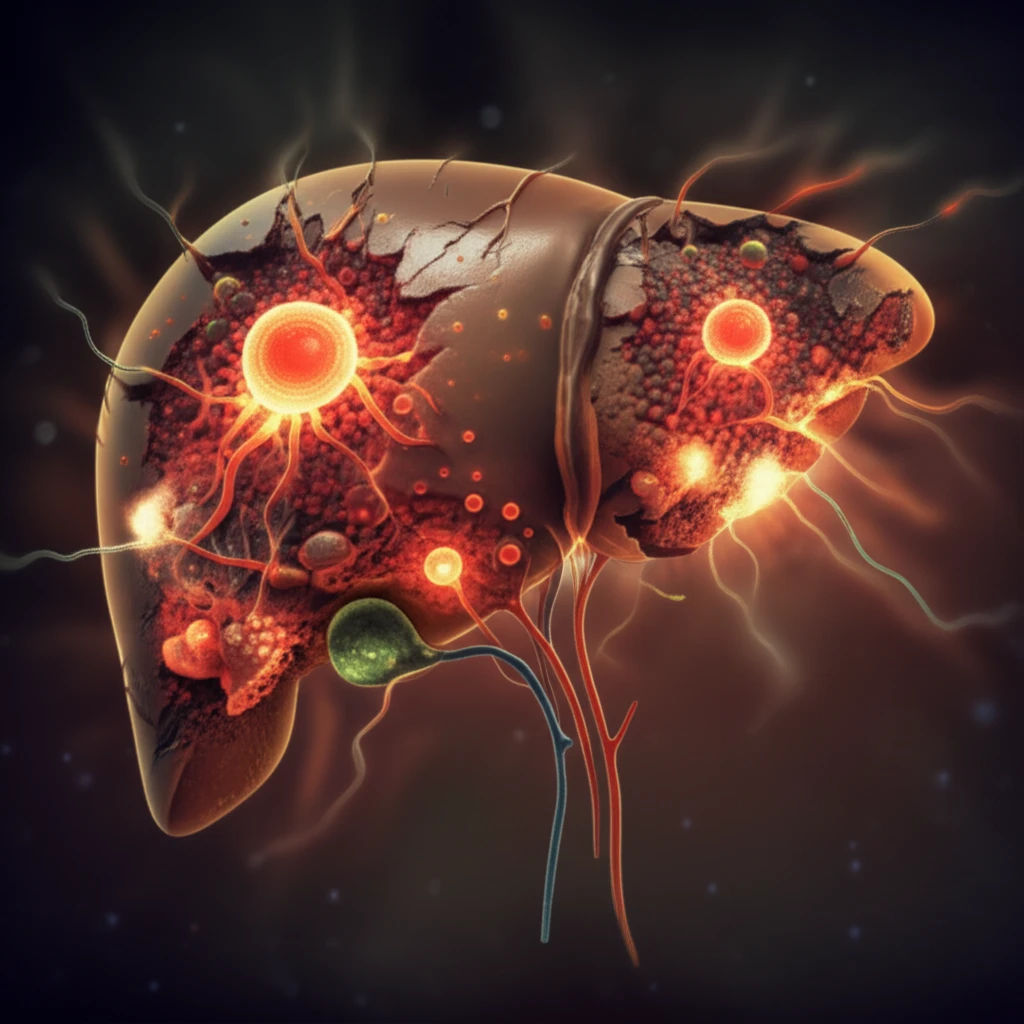

Liver disease poses a significant global health challenge, affecting over 450 million individuals through viral hepatitis and hepatocellular carcinoma (HCC). Traditional treatments, primarily liver transplantation, are often hindered by a severe shortage of donor organs, coupled with complications related to rejection and the necessity for long-term immunosuppression. This scarcity creates an ever-widening gap between the number of patients needing transplants and the availability of suitable organs.